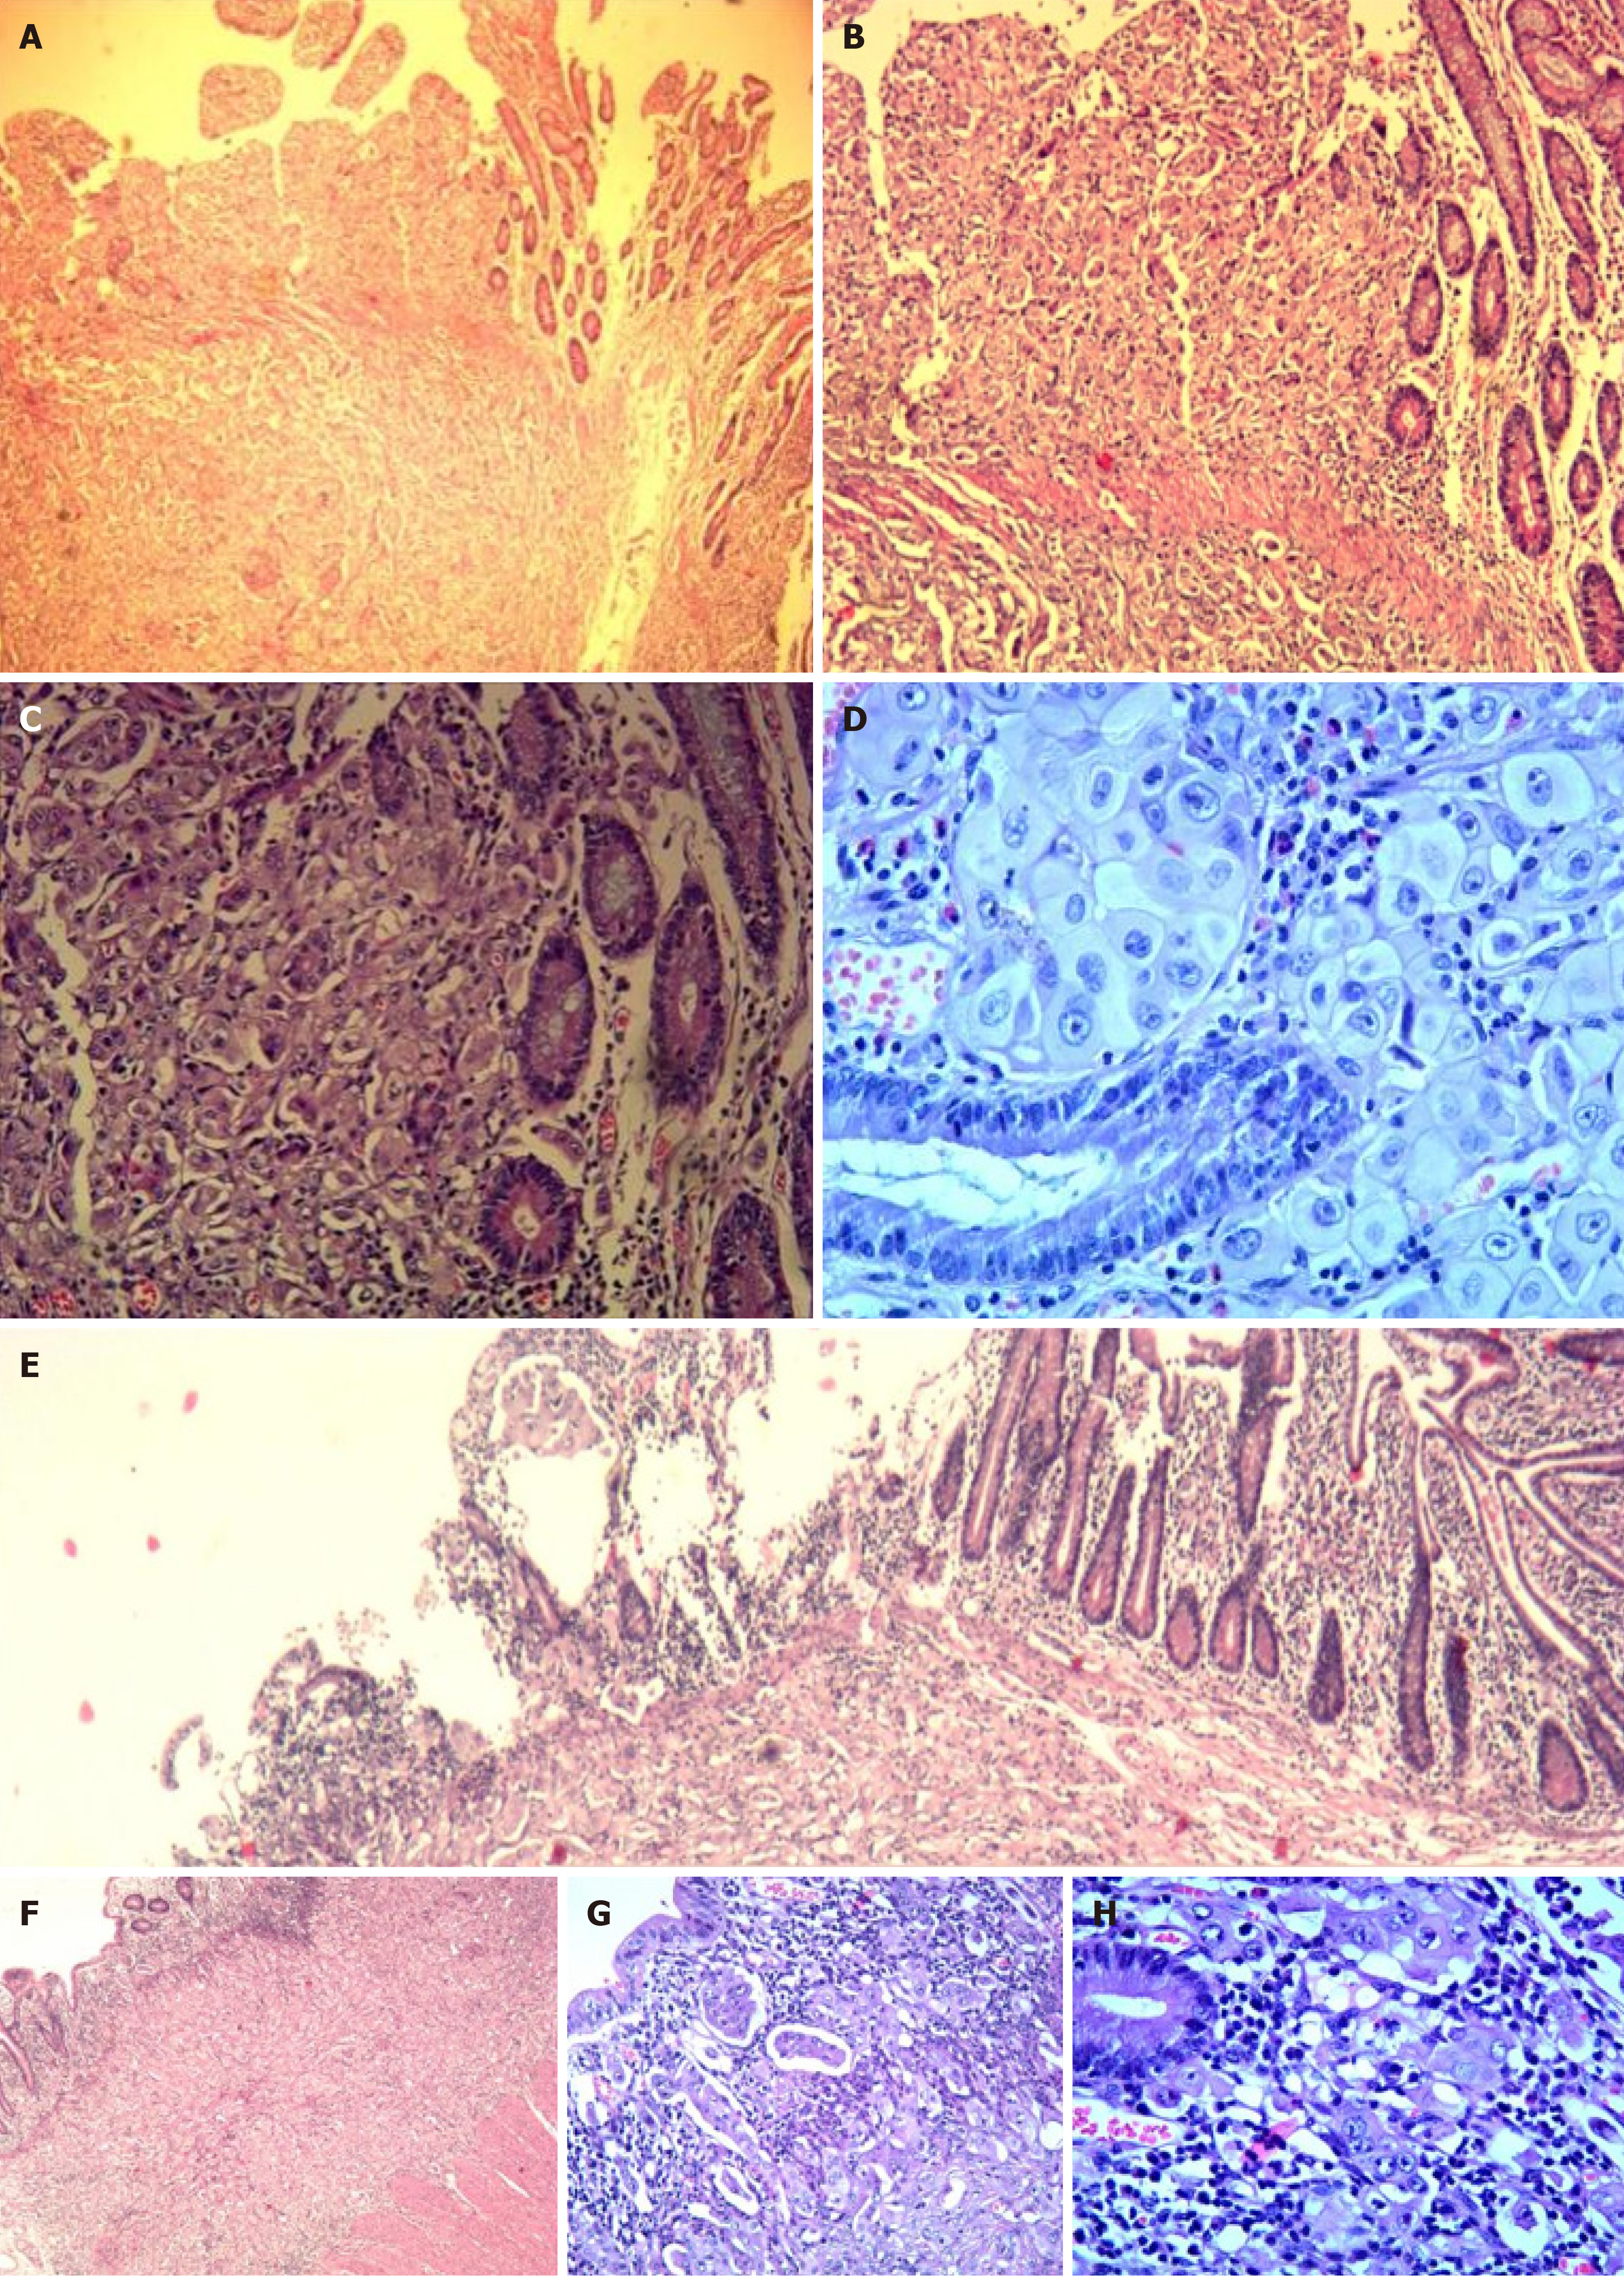

Figure 3

Figure 3 Small intestinal metastasis. A-D: First small intestine resection specimen. A: Hematoxylin-eosin × 40; B: Hematoxylin-eosin × 100; C: Hematoxylin-eosin × 200; D: Hematoxylin-eosin × 400; E-H: Second small intestine resection specimen (E: Hematoxylin-eosin × 40; F: Hematoxylin-eosin × 100; G: Hematoxylin-eosin × 200; H: Hematoxylin-eosin × 400).